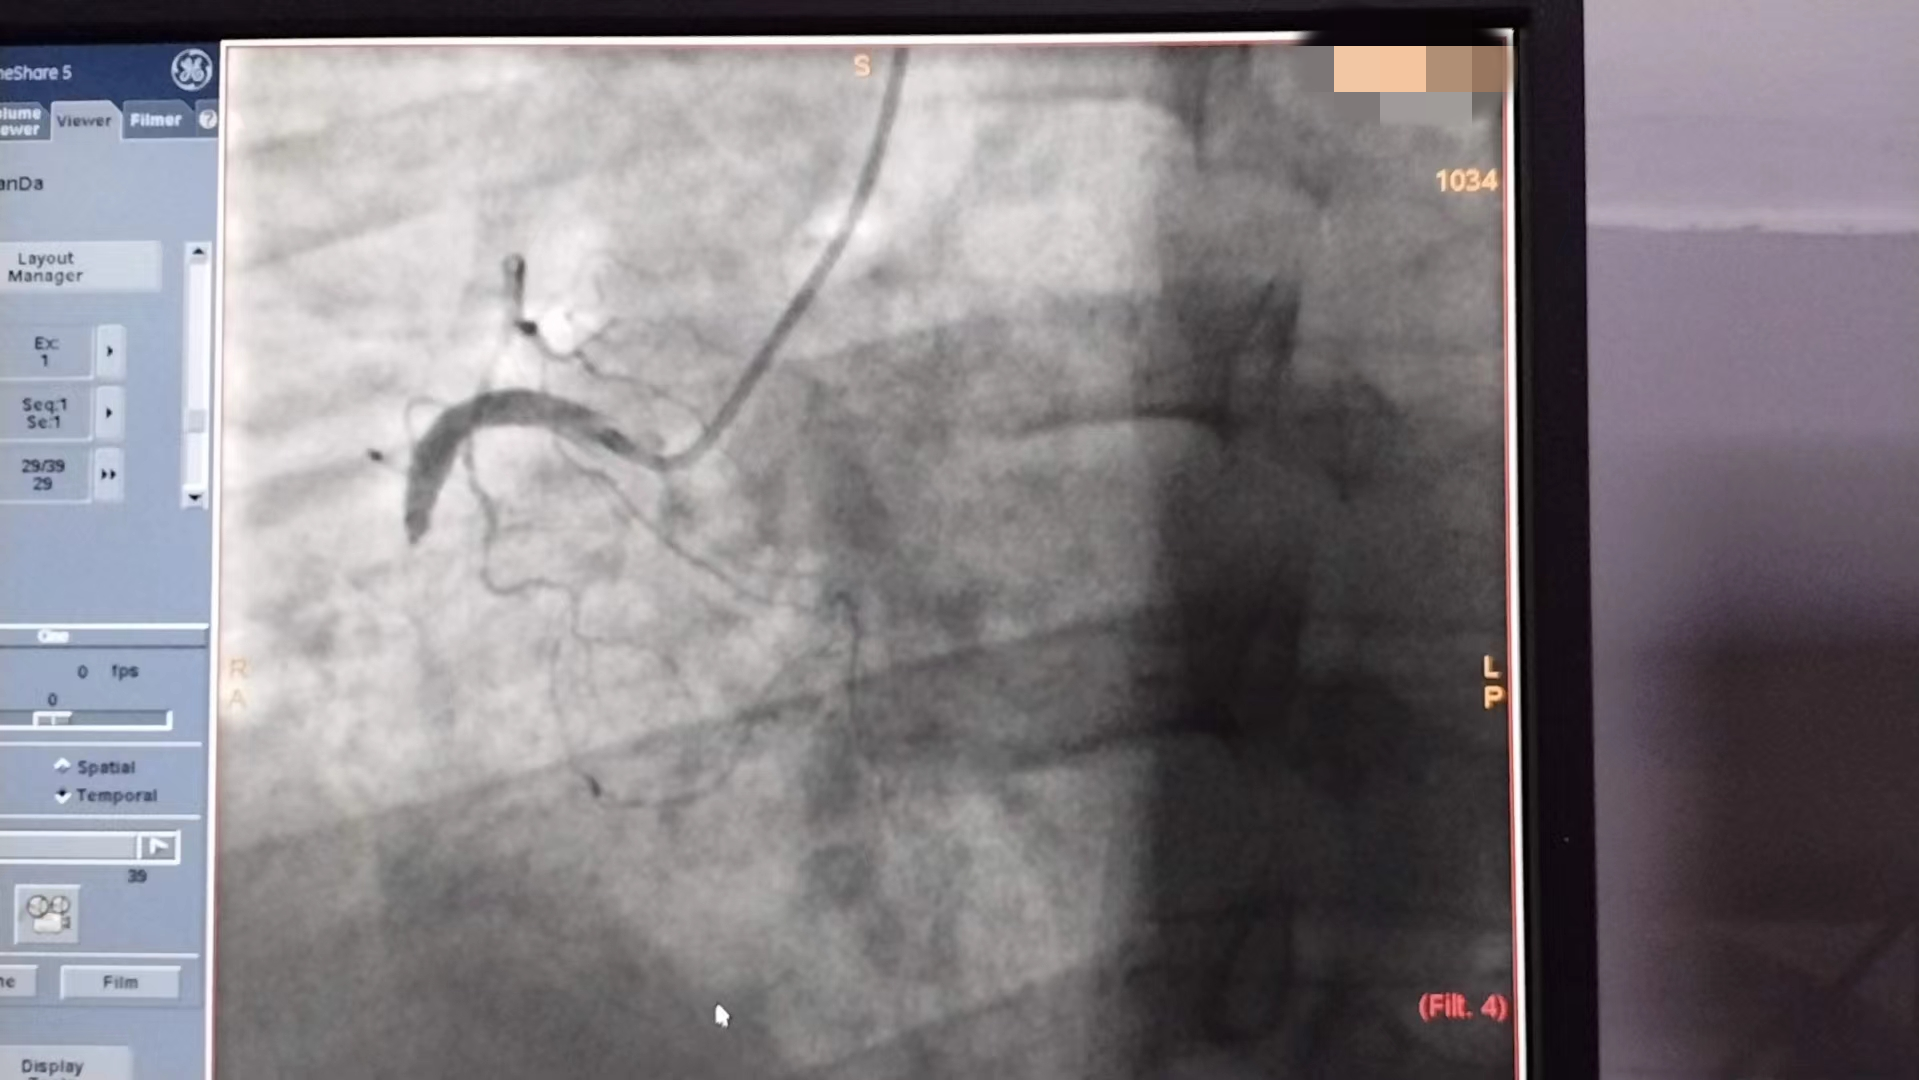

冠脉造影提示曾某右冠、前降支中段完全堵塞,病情相当危重,手术风险高,娄底市第二人民医院介入手术团队在曾某的充分信任和队员们的密切配合下,于90分钟内予以导丝通过闭塞血管、完成血运重建,至上午9点整顺利完成冠脉支架置入手术。术后曾某恢复良好。

术前